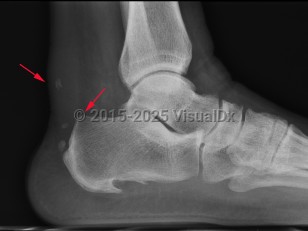

Achilles tendinosis / tendinopathy is tendon thickening in the region approximately 2-6 cm proximal to tendon insertion and is thought to be caused by poor blood supply and anaerobic degeneration of the cartilage.

Insertional Achilles tendonitis is pain and tendon thickening at insertion of the Achilles tendon, wherein repetitive trauma leads to inflammation followed by cartilaginous, bony metaplasia.

Haglund deformity is enlargement of the posterosuperior tuberosity of calcaneus. Retrocalcaneal bursitis is inflammation of the space between the anterior aspect of Achilles tendon and posterior aspect of calcaneus.